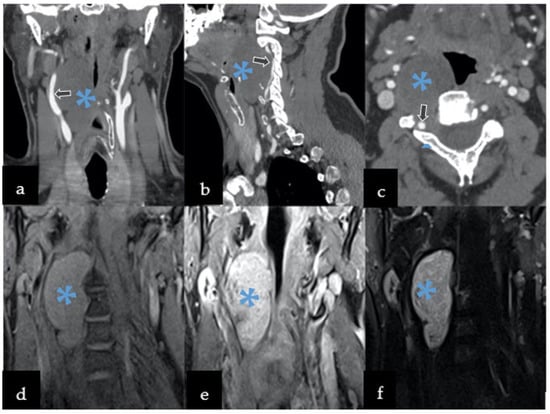

3.3. Radiological Features